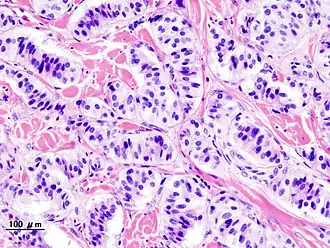

| Гистопатологическая картина панкреатической инсулиномы. | |